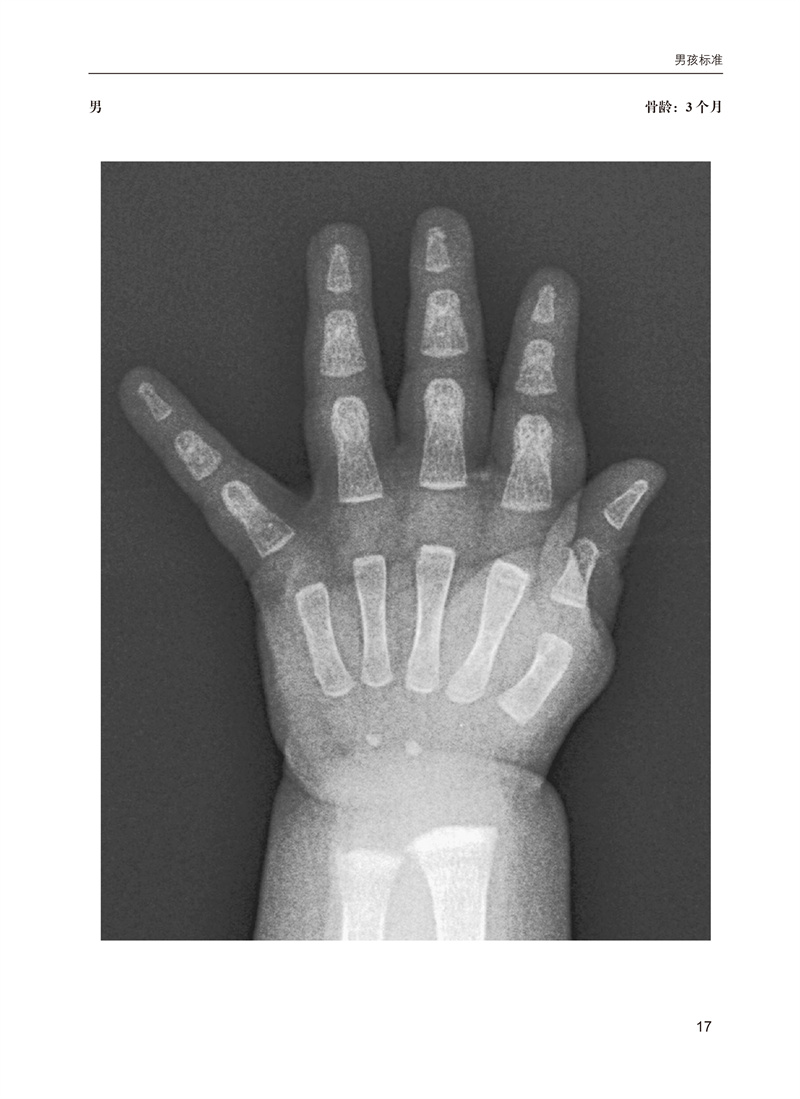

骨龄是国际公认的准确反应儿童生长发育的重要指标,也是临床医学、体育及法医学领域不可或缺的一项重要检查。本书基于广受欢迎的Greulich和Pyle图谱,将儿童骨骼成熟度的确定方法现代化。它提供了大量的图像,这些图像是从弗吉尼亚大学的PACS中的数千张数字X光片中精心挑选出来的,以最佳展示重要发育性骨特征,并按年龄和性别组织,以便快速参考。为了便于学习和临床图像分析,带注释和不带注释的图像成对出现,以便容易比较。图像上的简洁注释取代了冗长的文本,以提供更快速、更清晰的骨骼年龄标志。这些注释强调了重要而微妙的特征,帮助区分否则看起来相似的图像。本书分为两大部分:男性和女性各年龄段标准图谱。本书是一个高质量的左手腕X线片标准图谱,捕捉了Greulich和Pyle公认标准的重大和细微细节。鉴于骨龄应用的广泛性,手和腕部骨骼发育不仅旨在为实践和培训放射科医生提供参考,也适用于所有将骨龄研究作为实践一部分的人员。